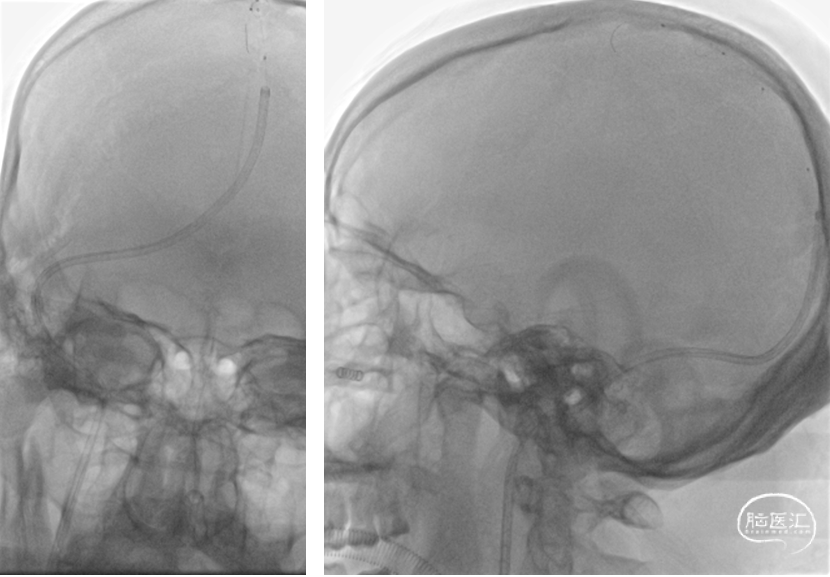

在Transend 300cm微导丝携带下将Wallstent7*40mm支架送至右侧横窦,定位准确后缓慢释放

复查造影右侧横窦显影良好,静脉回流明显改善,乙状窦显影仍欠佳

将Wallstent7*40mm支架沿中间导管送至乙状窦,定位准确后缓慢释放

复查造影:上矢状窦显影明显改善,右侧横窦及乙状窦显影良好,静脉回流良好

颅内正侧位造影:上矢状窦显影明显改善,右侧横窦及乙状窦显影良好,静脉回流良好

在微导丝导引下将Rebar18微导管置于上矢状窦,给予尿激酶25万 单位入50ml生理盐水中,以12ml/h持续微量泵泵入